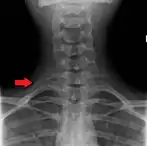

El número de costillas puede variar. Una de cada 200-500 personas tienen una costilla cervical adicional, siendo un caso predominante en las mujeres.[13] Las costillas supernumerarias intratorácicas son poco usuales.[14] En ocasiones, la costilla remanente de la 7ª vértebra cervical de uno o ambos lados se sustituye por una costilla adicional libre, denominada costilla cervical, la cual puede interferir de forma mecánica con los nervios (plexo braquial) conectados al brazo.

En 1543, el anatomista flamenco Vesalius notó el número de costillas, 24 (12 pares), en su obra clave de anatomía De humani corporis fabrica, lo cual desató una ola de controversia. Debido a la historia bíblica de Adán y Eva, se solía asumir que los hombres tenían menos costillas que las mujeres.[18][19] Sin embargo, solo el 1% de personas tiene la decimotercera o “costilla cervical”,[12] siendo más común de ocurrir en las mujeres que en los hombres.[13]

Imagen de rayos X del tórax humano, con las costillas marcadas.